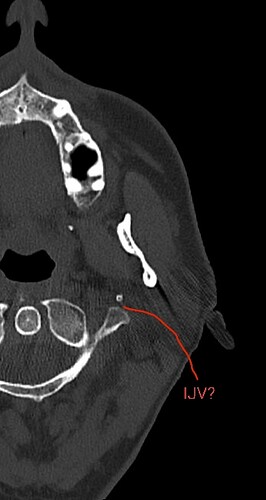

@tguerin18 did you happen to get a head/neck CT done? They are the best to look at vascular compression. If you did get one done, can you go to the axial view and go to C1? I attached my own imaging to help you know what to look for. Im less familiar with MRV, but I annotated your imaging. If I’m correct, your IJV is being compressed against your C1. Not sure if styloid is involved in the pinch or not. If you did get a CT done we will get to the bottom of it.

@tguerin18 see attached the annotated imaging. It appears your left ijv (right side of image) is compressed between your left styloid and C1. Since there is no matching white dot on the left side of the image, i suspect your left styloid is longer than your right and has caused a choke point for your left ijv between the styloid and C1. Since you don’t have contrast, I can’t say with 100% certainty the ijv is being compressed, but it is where the ijv is typically located.